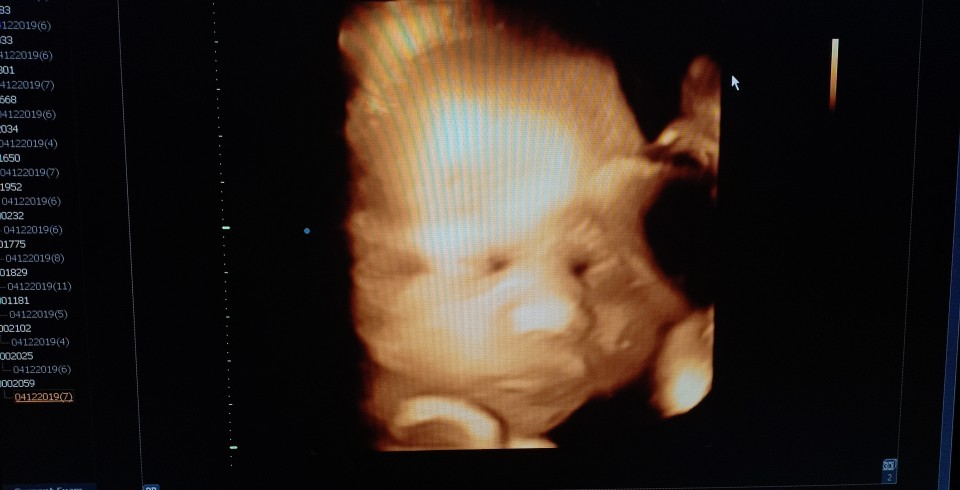

บ้านนี้ก็บังจ้าาาา